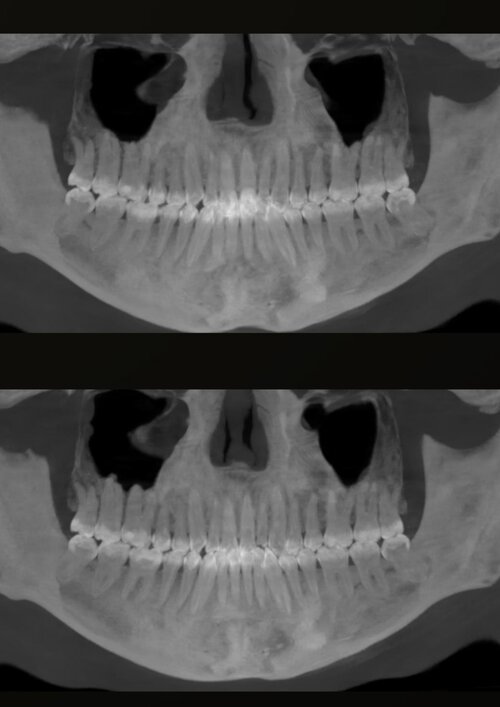

i have compressed airway (84mm smallest width), but doctors said i don't need surgery because i dont have sleep apnea.

also, they don't want to expand my palate because they said its only a little bit narrow so no worth the risk (upper palate 38.5mm, lower palate 42mm).

they want to extract my wisdom teeth to create space, and they said my overbite is gonna get fixed when they align my upper teeth, because they are blocking my lower jaw (my upper teeth grew inwards).

ill attach some photos, should i change ortho? what do i need really?